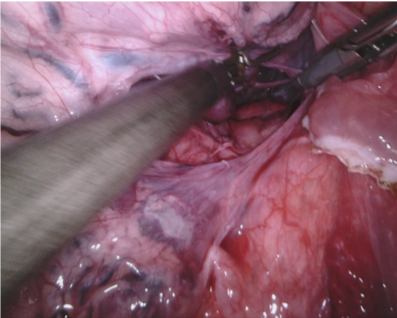

In 2017 we organized a follow-up challenge222https://endovissub2017-roboticinstrumentsegmentation.grand-challenge.org where a team at Intuitive Surgical manually segmented images from porcine robot assisted nephrectomy procedures. We aimed to improve on the previous challenge by first increasing the label quality by using hand-created labels rather than automatic labelling, secondly by adding greater variance in the background by using 10 separate procedures and finally by providing more type and part labels for the instruments.

Our dataset was made up of 10 sequences of abdominal porcine procedures recorded using da Vinci Xi systems. From each procedure we selected active sequences where significant instrument motion and visibility was observed and sampled 300 frames at a rate of 1 Hz. In cases where instrument motion ceased for several frames we manually removed these frames and extended the sequence so that exactly 300 frames remained. We provided left and right eye images from the stereo camera on the Xi system and also provided camera calibration information in case participants wished to use stereo reconstruction as a feature.

We provided the first 225 frames of 8 sequences as training data and kept the last 75 frames of those 8 sequences as test data. 2 of the full 300 frame sequences were kept as test sequences. Test labels were kept hidden from the participants. Our datasets contain 7 different robotic surgical instruments. The Large Needle Driver, Prograsp Forceps, Monopolar Curved Scissors, Cadiere Forceps, Bipolar Forceps, Vessel Sealer and additionally a drop-in ultrasound probe, which is typically held in the jaws of the Prograsp Forceps instrument. Samples from the training datasets are depicted in Fig. 2 and examples of the different instrument types are shown in Figure 3 and 4.

In Fig. 10 we show qualitative results of randomly chosen frames from each dataset. In the top row, we show frame 278 from dataset 1, which contained 2 Prograsp Forceps instruments and a drop in ultrasound probe. The 3 selected frames were from methods that all averaged over 0.8 mean IoU yet showed considerable difference in their ability to differentiate the US probe. There was also visibly different performance across the methods in dataset 7, which contained a Vessel Sealer and complex lighting.